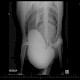

Abb.1 - Unfall-Aufnahme: Patient männlich 29 J. – Fußballer: Nach Kopfball beim Auftreten mit dem linken Bein weggerutscht. Klinisch hochstehende Patella. Anheben des gestreckten Beins nicht möglich. Im Röntgenbild Patellahochstand sowie Verdickung der Patellarsehne mit Verkalkungen.

Die Diagnose kann meist schon aufgrund des klinischen Befundes sicher gestellt werden: Es findet sich eine Unfähigkeit, das Kniegelenk aktiv gegen Widerstand zu strecken, der typische „Patellahochstand“, das gut tastbare „Hochwandern“ der Kniescheibe bei Beugung im Knie oder Anspannung der Oberschenkel-Streckmuskulatur sowie das ebenfalls gut tastbare „Fehlen“ der Patellarsehne. In einzelnen Fällen reißt die Sehne nicht selbst, sondern es liegt eine sogenannte „Abrissfraktur“ aus dem Schienbeinhöcker oder dem unteren Kniescheibenpol vor, die auf einem konventionellenRöntgenbild gut sichtbar ist.

Der akute komplette Verlust der Streckfähigkeit des Kniegelenks kann neben der seltenen Patellarsehnenruptur auch durch eine viel häufigere Patellafraktur verursacht sein. Auch hier ist eine höhere Position der Kniescheibe oder eines Teils davon tastbar. Eine seitliche Röntgenaufnahme des Kniegelenks bringt eine sichere Abgrenzung in Form der Bestätigung oder des Ausschlusses einer knöchernen Beteiligung. Durch diese Röntgenaufnahme können auch sichere Hinweise auf eine als Differentialdiagnose mögliche Quadricepssehnenruptur gefunden werden: Der Tiefstand der Kniescheibe bei akutem Streckdefizit.